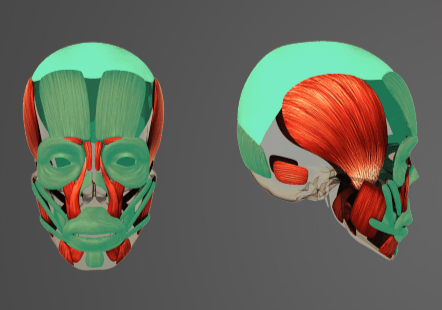

-

Question of

Určete:

-

svaly mimické

-

sval tylní

-

sval licní velký a malý

-

sval trubačský

-